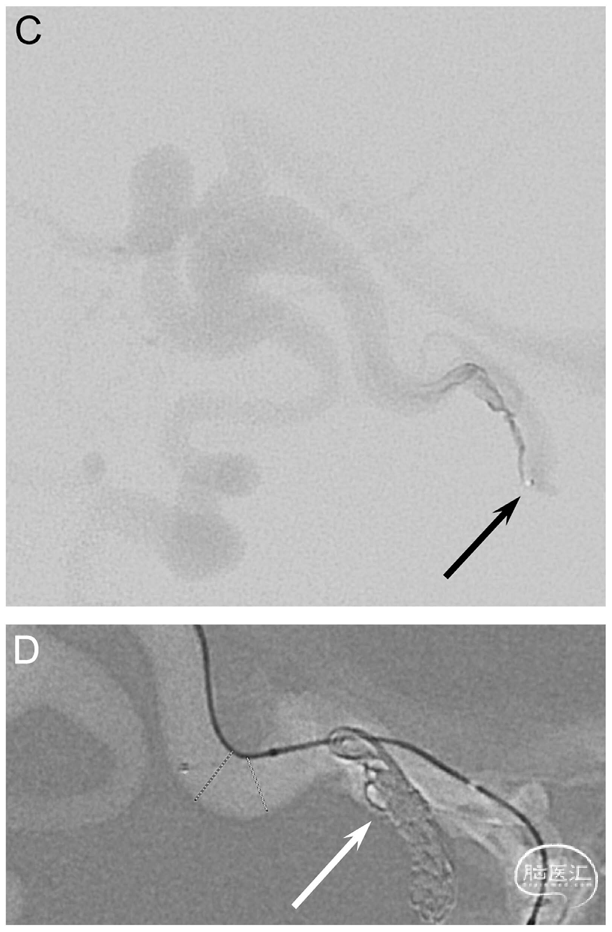

Fig. 1. A 52-year-old woman (patient no. 3) with headache and pulsatile tinnitus underwent an MRI showing dilated veins in the posterior fossa. A diagnostic DSA confirmed a high-grade tentorial DAVF near the confluence (Borden type III, Cognard type IV). A.-B. Left CCA and left selective posterior meningeal artery (PMA) injections in lateral views show a DAVF (arrow) with deep venous drainage and several venous ectasias. C. Lateral view showing the transfistulous approach performed via the left PMA using a triaxial system with a 5F Sofia and a 1.3F Headway™ Duo (Terumo Neuro) reaching the proximal venous outflow (arrow). D.-E. Roadmap in lateral views. The fistulous outflow consisted of two adjacent, first separately draining and then merging veins, both of which were tightly packed with coils (arrows). Due to the high flow, the 2nd and more enlarged distal portion (E) required an oversized HydroCoil18 (10 mm x 31 cm, Terumo Neuro) for a stable basket to be filled with smaller Target XL coils (Stryker). F. Late-phase left ICA control run in lateral view shows formation of thrombus in the dilated draining vein as a filling defect (arrow). G. Left occipital artery control run in lateral view shows complete occlusion of the arteriovenous shunting. Follow-up DSAs showed near-complete occlusion after 3 months and complete occlusion after 9 months (not shown).